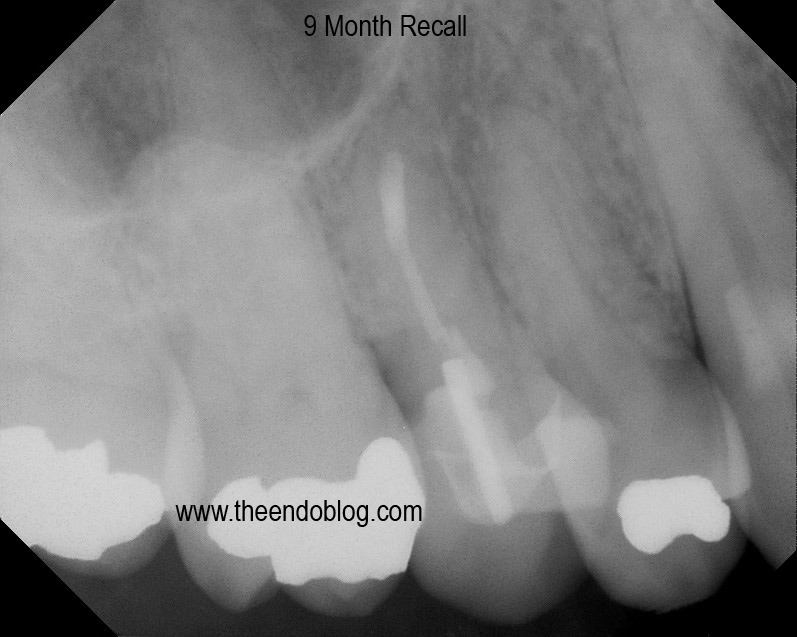

This root canal was done by her general dentist 3 months earlier.  As you can see it is overfilled, post placed, crown prepped and ready for new crown, but patient continues to have symptoms with the tooth.

CBCT taken to evaluate the root morphology. It is clear that this is a single root/canal.  (The canal has an oblong shape)  It was chosen to treat this tooth with apical surgery to preserve the restorative work that has been completed and assure that the overextened gutta percha is removed.

Apicoectomy completed with MTA retrofill.

9 month recall show complete healing of the periapical lesion, tooth is fully functional and asymptomatic.  This procedure saves the patient significant time and money over extraction and implant placement.